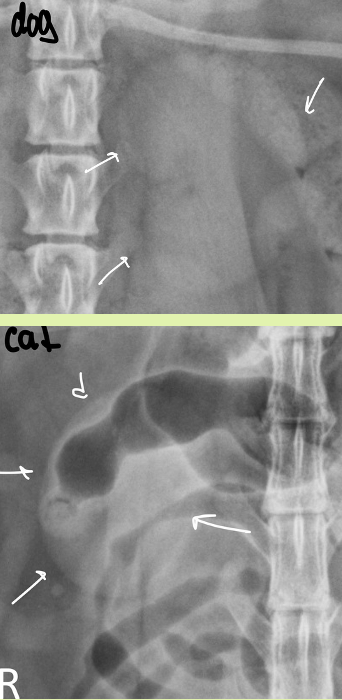

what might you see in the renal pelvis region of cat that is different from dog kidneys

peripelvic fat

shape of kidneys dog vs cat

dog - bean

cat - oval